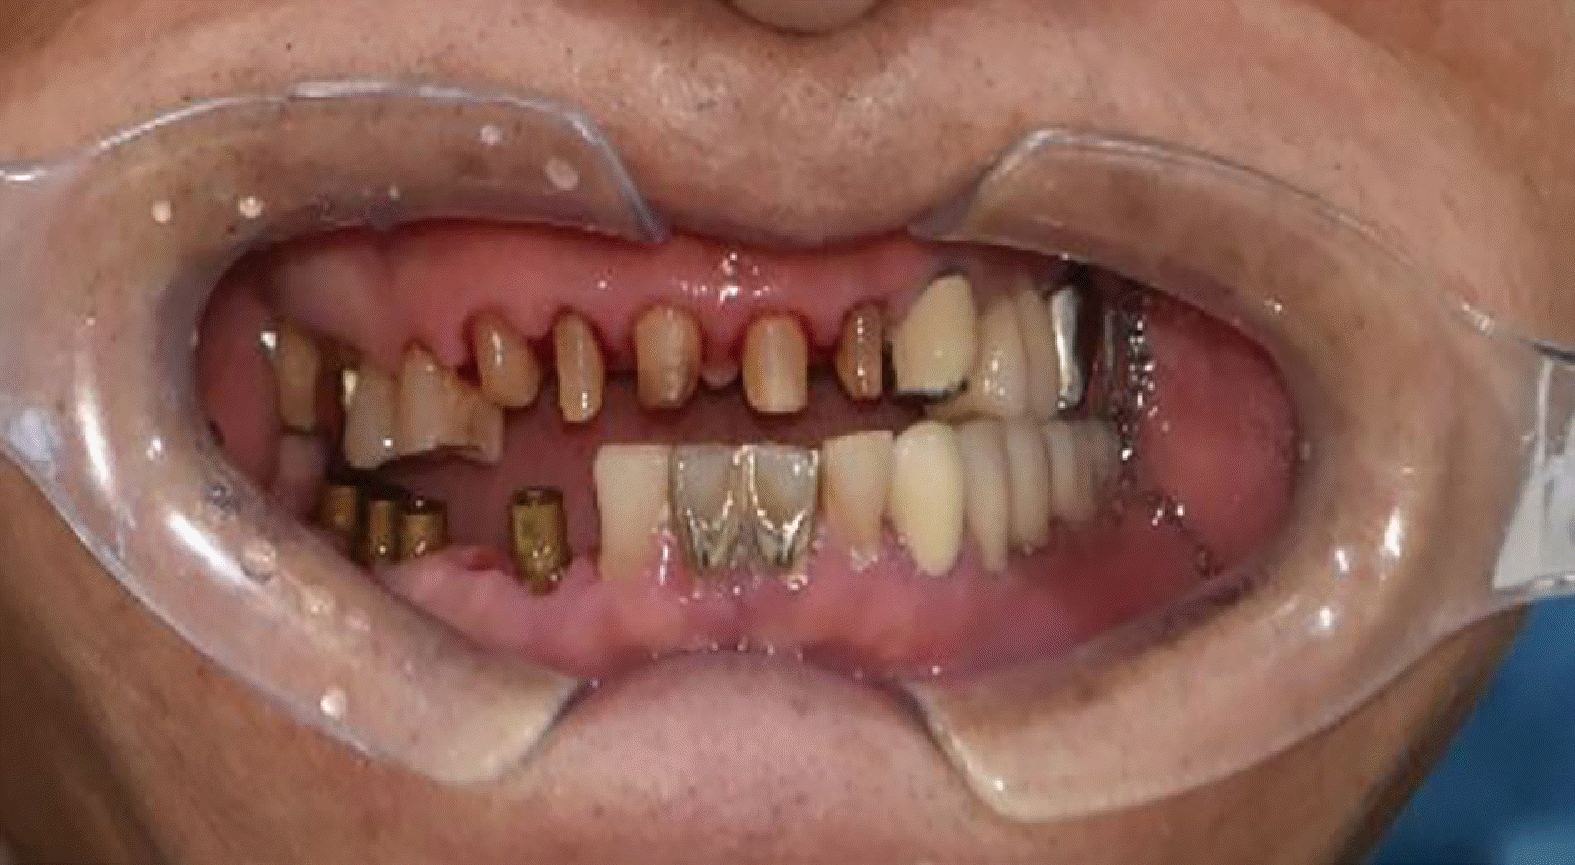

Fig. 2

Initial oral examination. Severe attrition of both maxillary and mandibular anterior dentitions with anterior cross-bite is shown.

At the initial visit, the patient exhibited a skeletal Class III relationship with edge-to-edge incisal contact in CR guided by chin-point technique (Fig. 1). TMJ assessment showed normal mouth opening (> 40 mm) without joint or muscle symptoms, and no signs of popping, crepitus, or pain on loading test (per Dawson).7 Habitually, the mandible closed anterosuperiorly, with the mandibular incisors sliding along the labial surfaces of the maxillary incisors (Fig. 2). Treatment commenced with the mandible guided into CR, achieving stable anterior end-to-end contact at the appropriate vertical dimension.